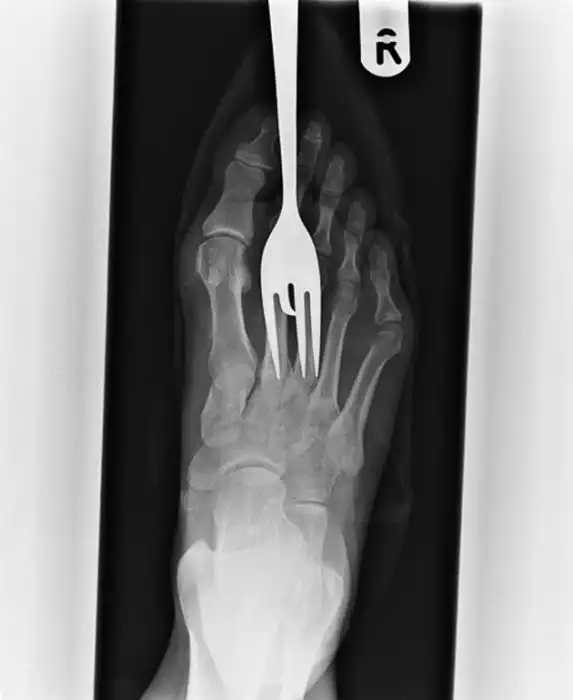

Порой даже не верится, с какими странными и необычными повреждениями в травматологию могут поступить пострадавшие. Всю эпичность профессии врачей травматологии могут с легкостью подтвердить рентгеновские снимки.